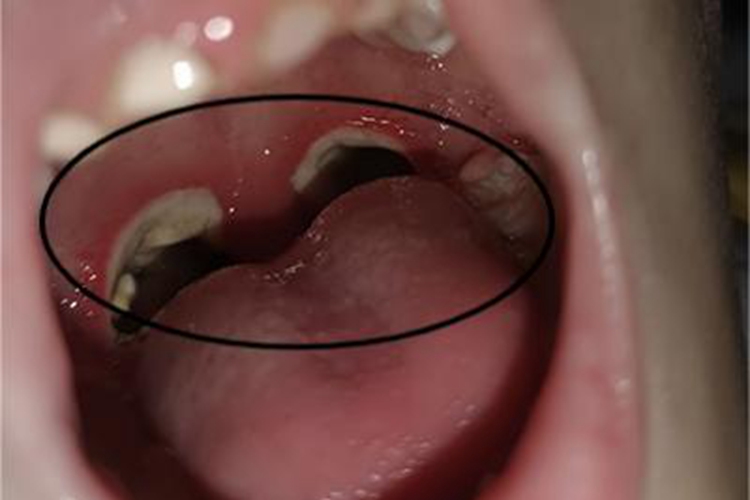

化脓性扁桃体炎可观察到患者咽喉部位出现化脓症状,患处肿大、充血,表面有脓性分泌物,可连接成片,呈伪膜状,易于揩去,不留出血创面。同时可伴有高热、全身不适等症状。